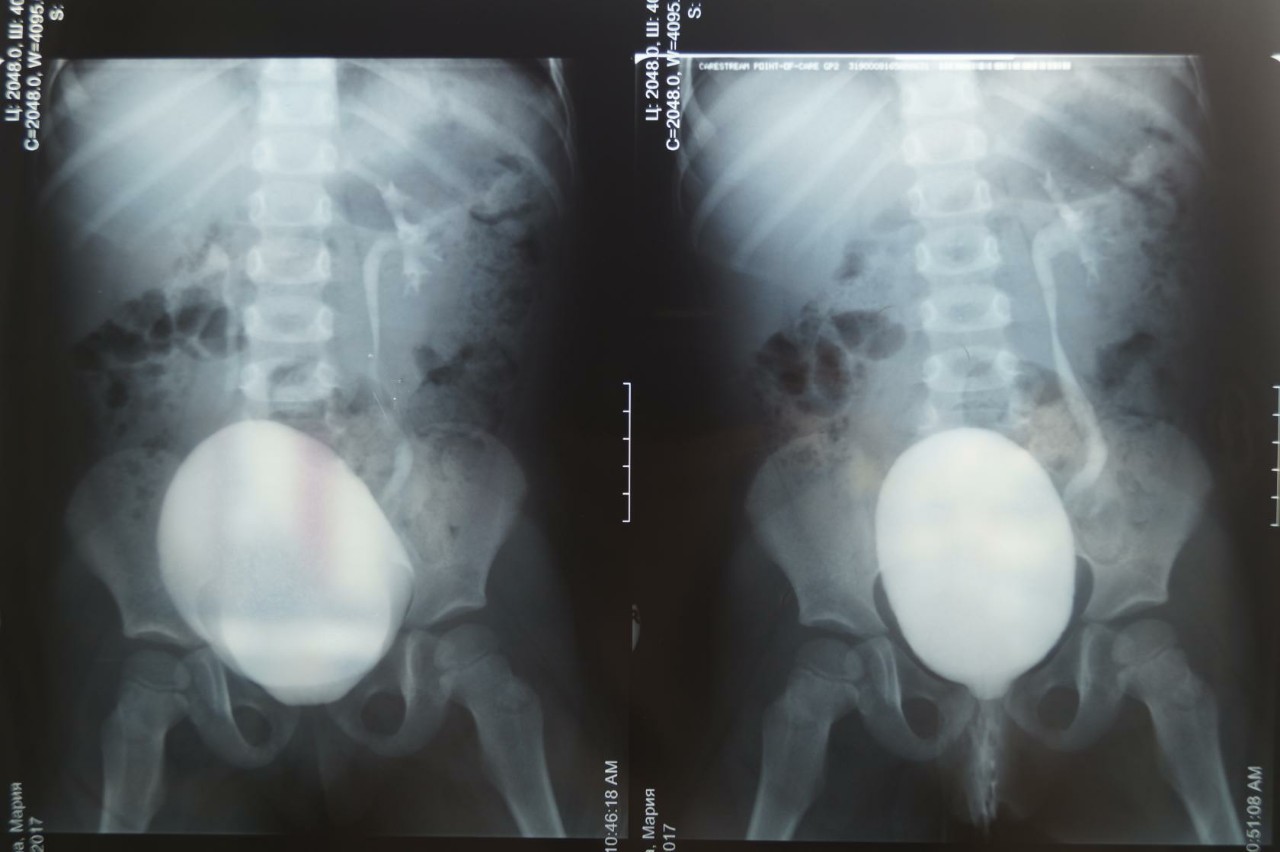

Рефлюксирующий мегауретер: Визуализация и медицинские изображения

Раздел: Фотопуть к знанию